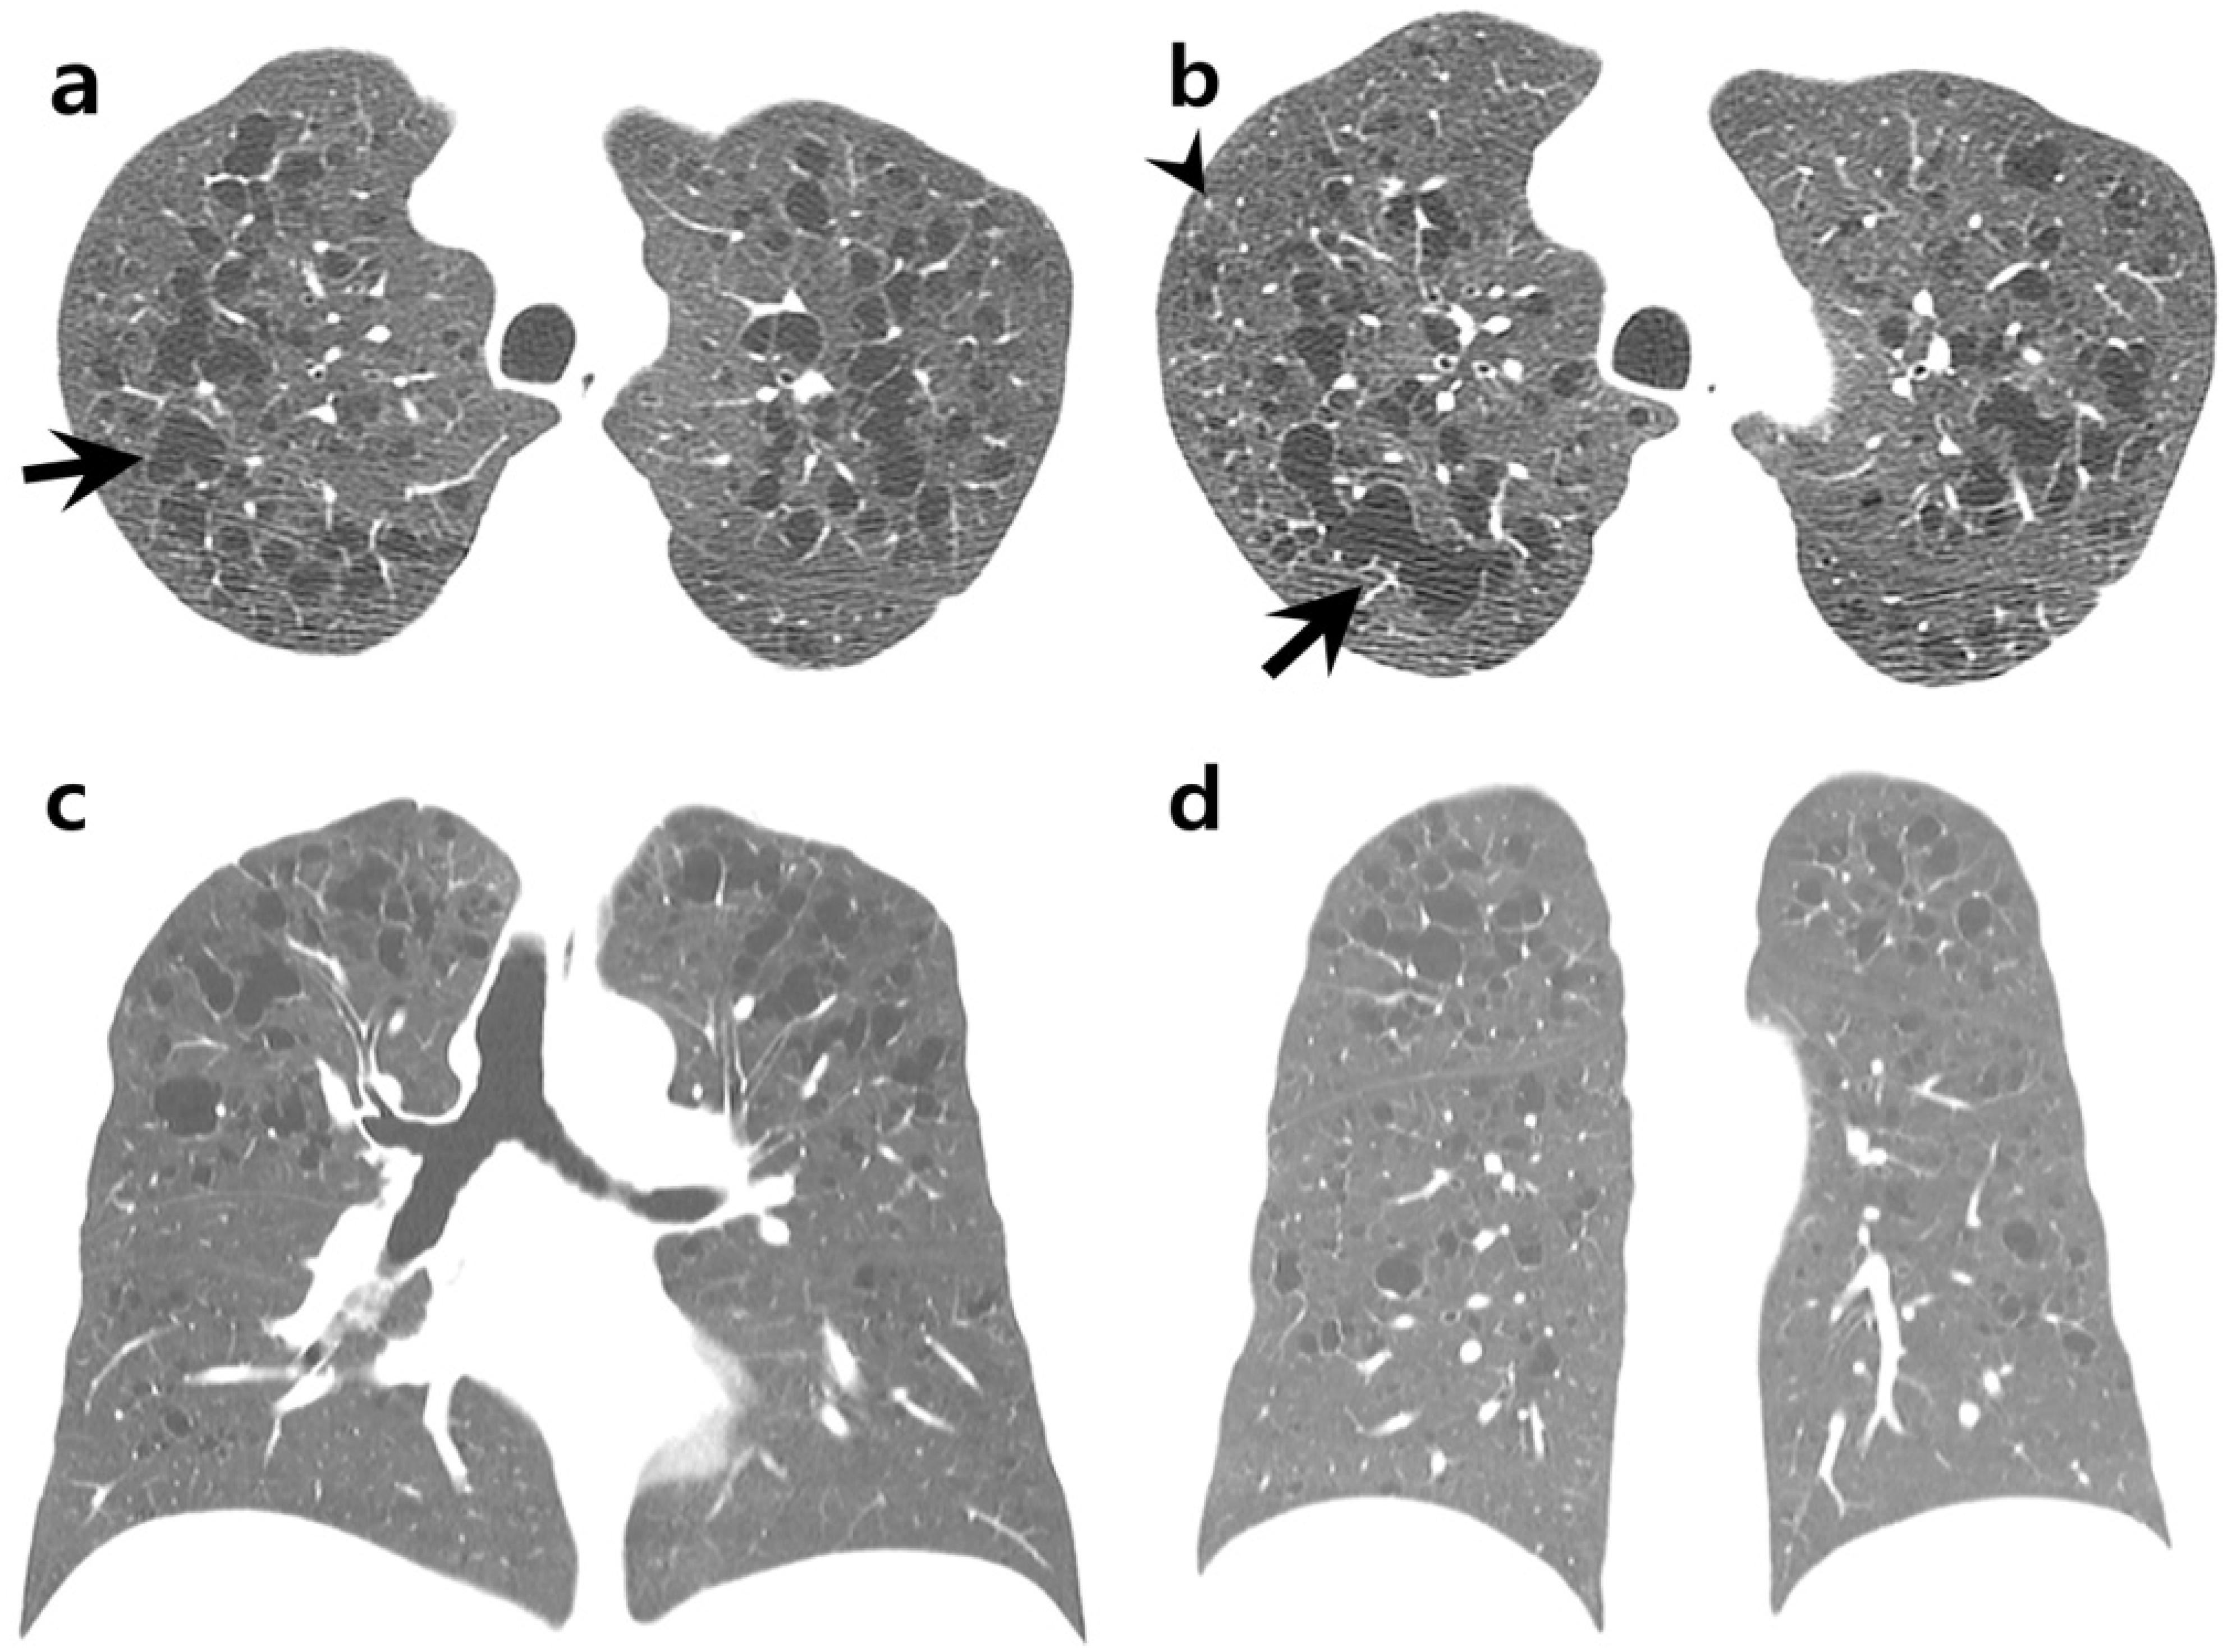

Airspace Enlargement with Fibrosis in a Young Heavy Smoker Mimicking Diffuse Cystic Lung Disease